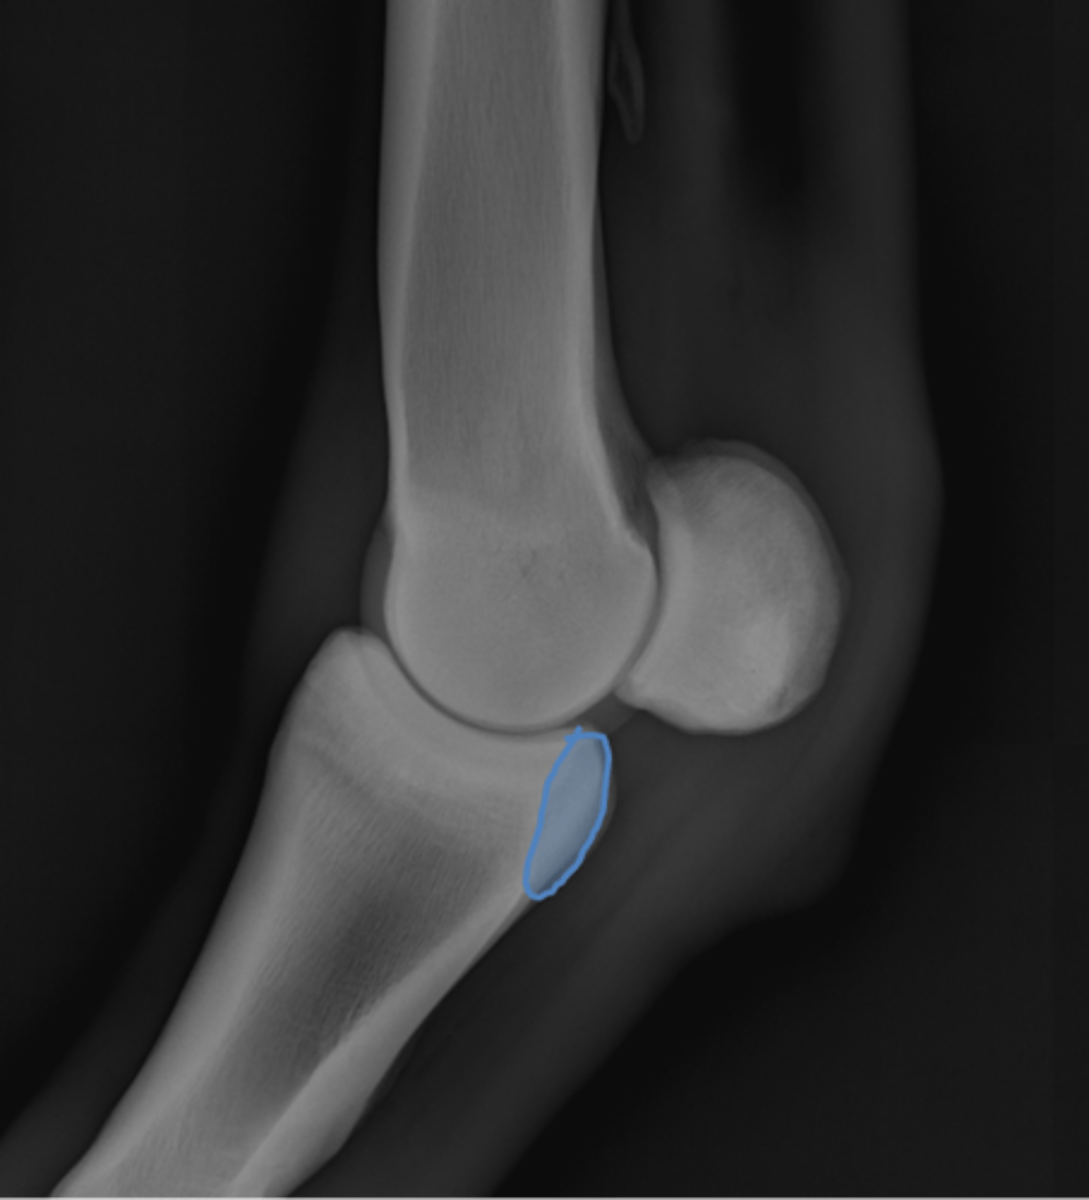

Fetlock joint, LM

ID joint and view

Fetlock joint, flexed LM

ID joint and view

Proximal sesamoid bone

Sagittal ridge

Condyles of third metacarpal bone

Palmar process of P2

Proximal sesamoid bones

Sagittal ridge

Attachment of collateral ligaments

Proximal sesamoid bones

Palmar process of P1

Condyles of the third metacarpal bone